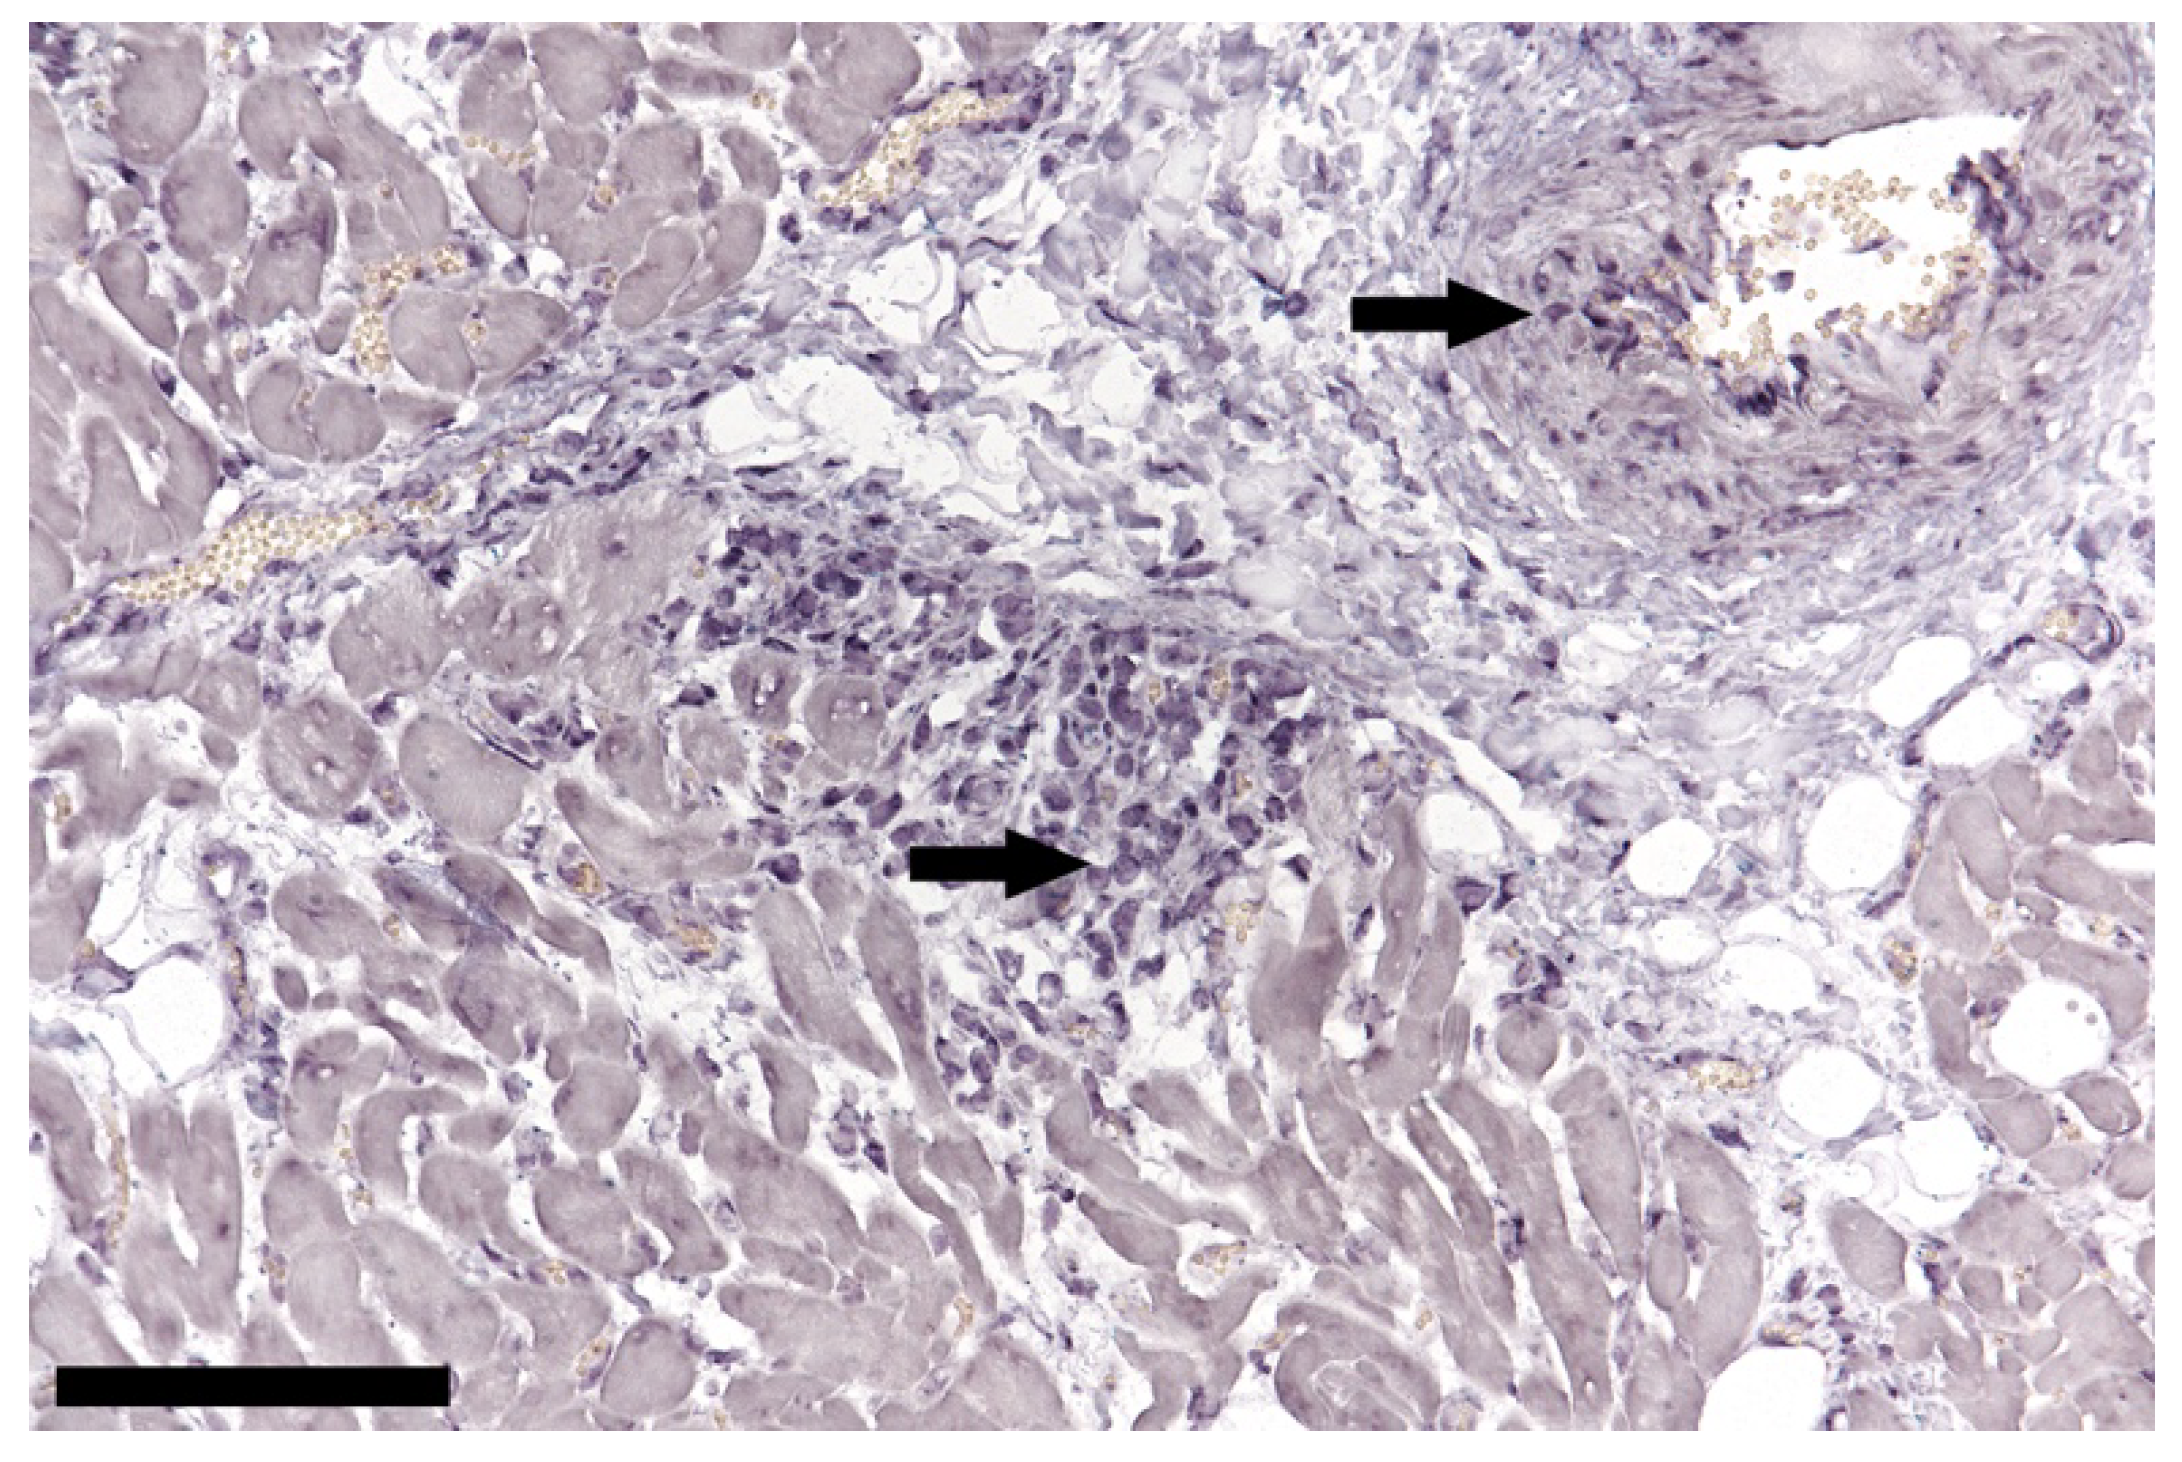

3.2. TTSuV1 Detection by DNA ISH and Immunohistochemical/Histochemical Investigation of the Porcine Brain